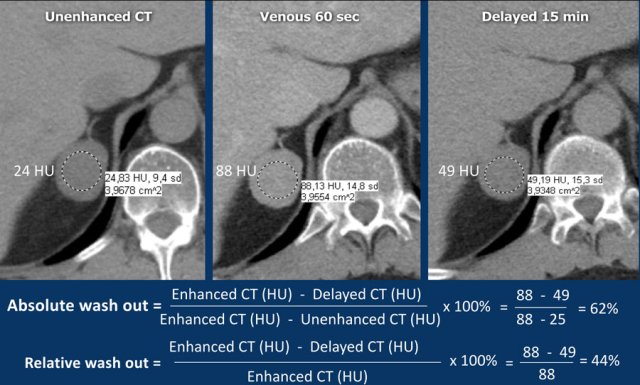

A dedicated adrenal washout CT protocol consists of a non-contrast, a contrast -enhanced scan with a delay of 60-90 sec and a delayed scan at 15 minutes.

The ROI should encompass at least 2/3 of the lesion to ensure a representable assessment.

Absolute enhancement wash out ⩾ 60% is proof of an adenoma [5,6,8].

Relative washout

If an adrenal lesion is discovered on an enhanced scan while the patient is still on the table, then a second scan of the adrenals at 15 minutes after contrast injection can be made and the relative washout can be calculated.

Relative enhancement wash out ⩾ 40% is proof of an adenoma [5,6,8].

The images show an indeterminate lesion on the nonenhanced CT (density 24 HU).

The absolute washout in this patient is 62%.

This means that the lesion is a lipid-poor adenoma.